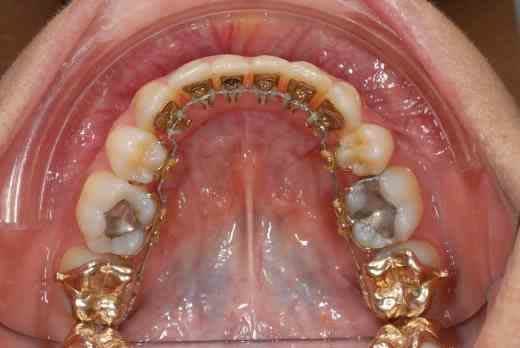

3 mois de mini vis et d'élastocs de classe II :-))

chuis pas belle comme ça? :-)))

la technique linguale est plus difficile à maîtriser, les points d'appui plus difficiles à trouver (cf minivis qui doivent rester esthétiques, c le but du traitement)